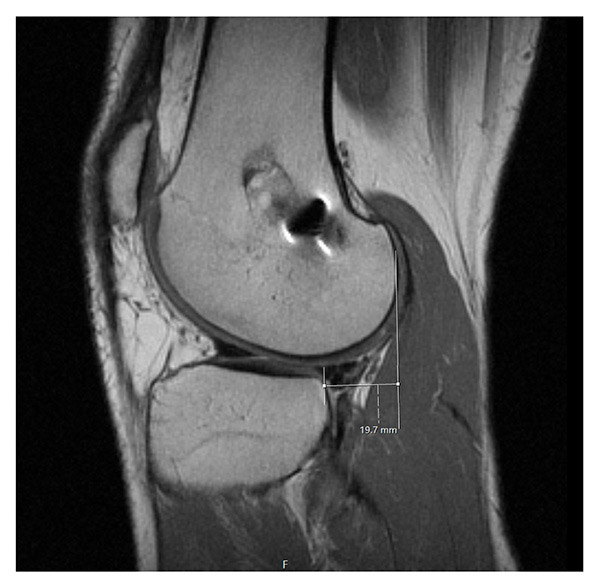

Physical examination demonstrated neutral alignment, a 3B Lachman test, and a grade-3 pivot shift. Collateral ligaments were stable with minimal medial opening to valgus stress. He lacked 2° to full extension and flexed to 135°. Preoperative imaging demonstrated increased posterior slope to approximately 17°, an absent ACL, and multiple fixation devices from his prior surgeries (Figure 1). A vertical tear in the posterior horn of the medial meniscus and an anterior subluxation of the tibia were noted (Figure 2). The articular surfaces were intact.

Figure 2: Preoperative right knee MRI demonstrates 19.7 mm of anterior tibial subluxation.